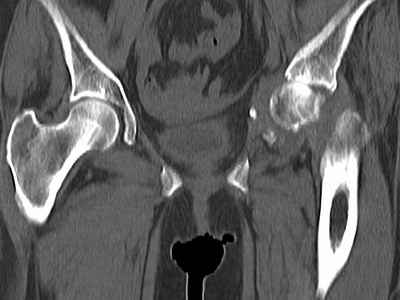

Уважаемые коллеги, возник вопрос по лечению нашей пациентки 60 лет. Около года назад множественная травма: в том числе Т-образный перелом вертлужной впадины. На сегодняшний день сращение отломков имеется на ограниченных участках, имеется дефект задней колонны вертлужной впадины. Движения неплохие, ходит с костылями, приступая на ногу. По мнению эдопротезистов при установке антипротрузионного кольца или октопуса не хватит костного материала и необходимо перед протезированием выполнить реконструкцию впадины, иначе чашка протеза неминуемо выпадет.Просьбы поделиться положительным и отрицательным опытом протезирования в подобных случаях.Возможно ли обойтись без реконструкции?Или лучше с ней?С уважением РАВ.

По моему мнению предварительну реконструкцию делать нет необходимости. Операцию надо выполнять одномоментно с пластикой вертлужной впадины. по поводу того, что не хватит головки. Да не исключено. Но ведь есть и другие материалы. Лучше при таком раскладе иметь в запасе замороженную головку. если нет возможности, как вариант два крыла подвздоной кости + хронос или его аналоги. По поводу выбора конструкции. Октопус в данной ситуации будет совсем не уместен, т.к. имеется дефект задней колонны вертлужной впадины. Да как конструкция октопус встанет не плохо. Но в функциональном плане не будет хорошей задне латерально и заднемедиальной точек опры впадины на период перестройки трансплатов. И по этому в данной ситуации более уместно кольцо Бурх(г)-Шнайдера с аналогичной пластикой, но возможнотью зафиксировать отломки задней колонны, крыши. Естественно цементная чашка с козырьком из кросс линк полиэтилена. Гололвка керамика, ножка бесцементная можно Цваймюллера или любой другой конструкции, они сейчас все хороши.